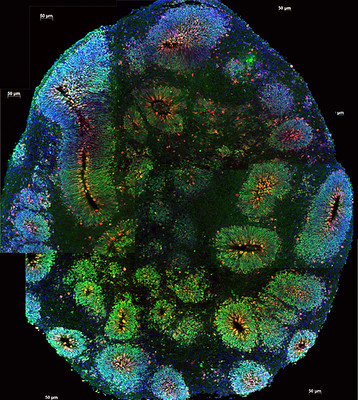

How “little brains” may help us treat brain cancer

Developing organoids from a patient’s brain tumor may help to understand how to treat them